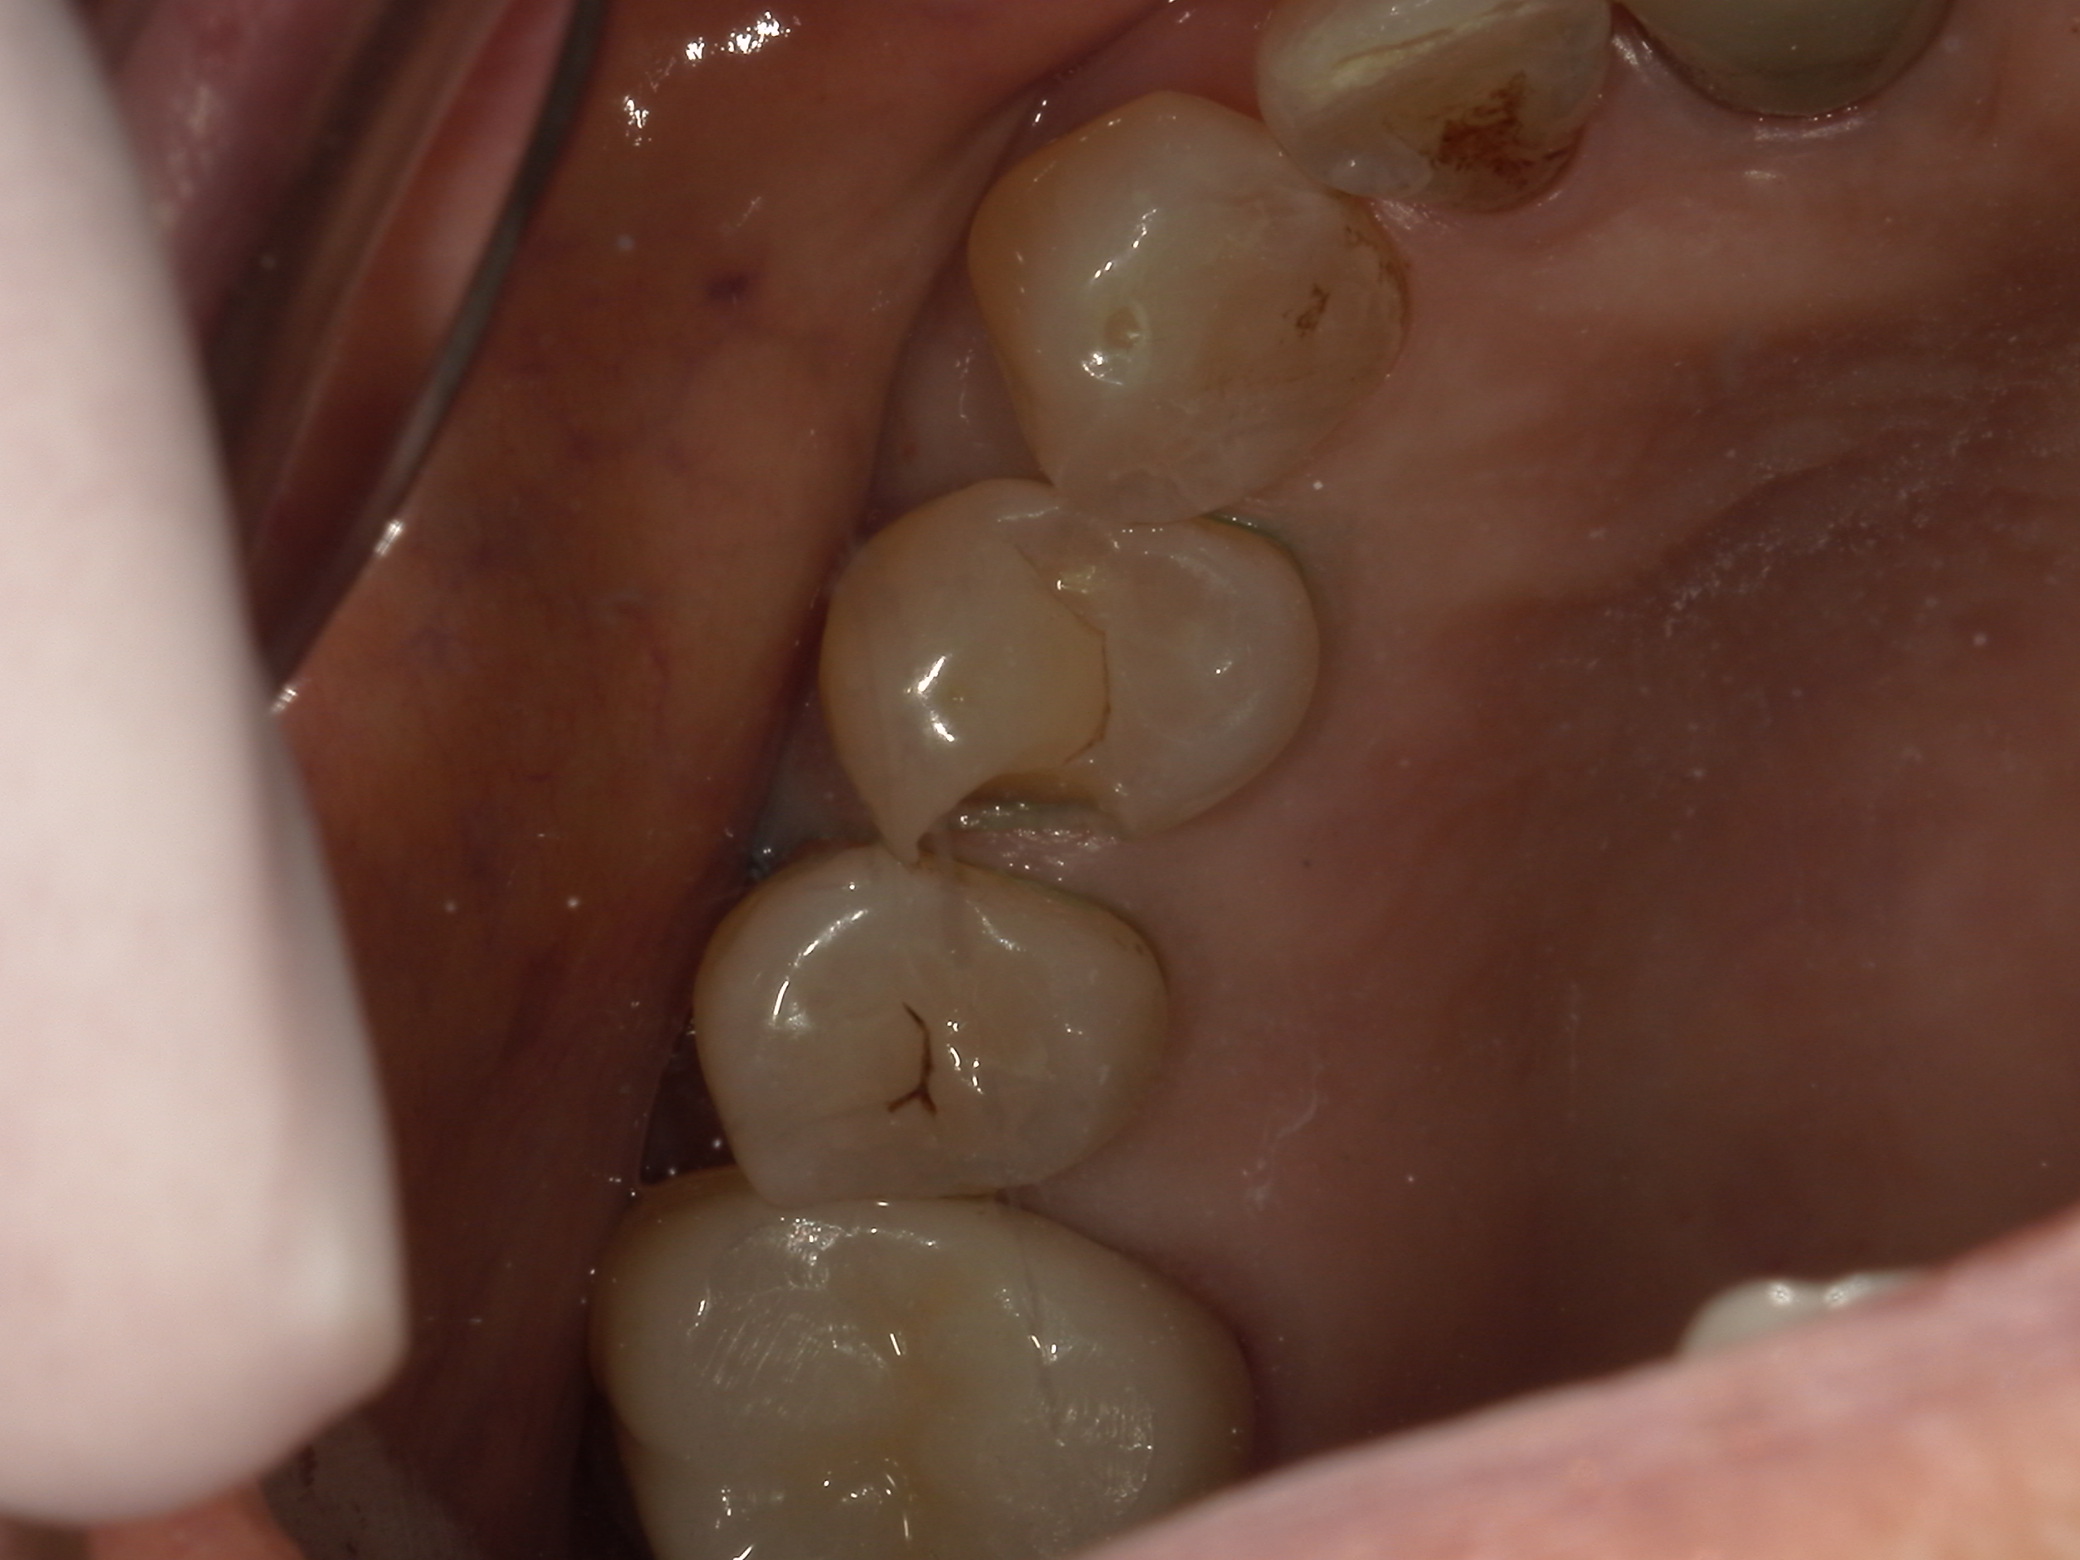

このような症状で来院される方は少なくありません。奥歯の痛みというと虫歯を思い浮かべる方が多いですが、ズーンとした鈍い痛みは虫歯以外が原因のことも多いのが特徴です。

奥歯の痛みには「ズキズキ」「しみる」「噛むと痛い」などいくつかのタイプがあります。その中でもズーンとした痛みは、次のような特徴を持つことが多いです。

原因① 虫歯(初期〜進行途中)

虫歯が神経に近づいてくると、いきなり強い痛みではなく、まずはズーンとした鈍い痛みとして感じることがあります。冷たいものがしみる症状がはっきりしない場合でも、内部で進行しているケースがあるため注意が必要です。

原因⑥ 歯のヒビ(クラック)

小さなヒビでも、噛むたびに力が加わると痛みが出ることがあります。最初は「噛むと少し痛い」程度でも、進行するとズーンとした違和感が続くようになることがあります。